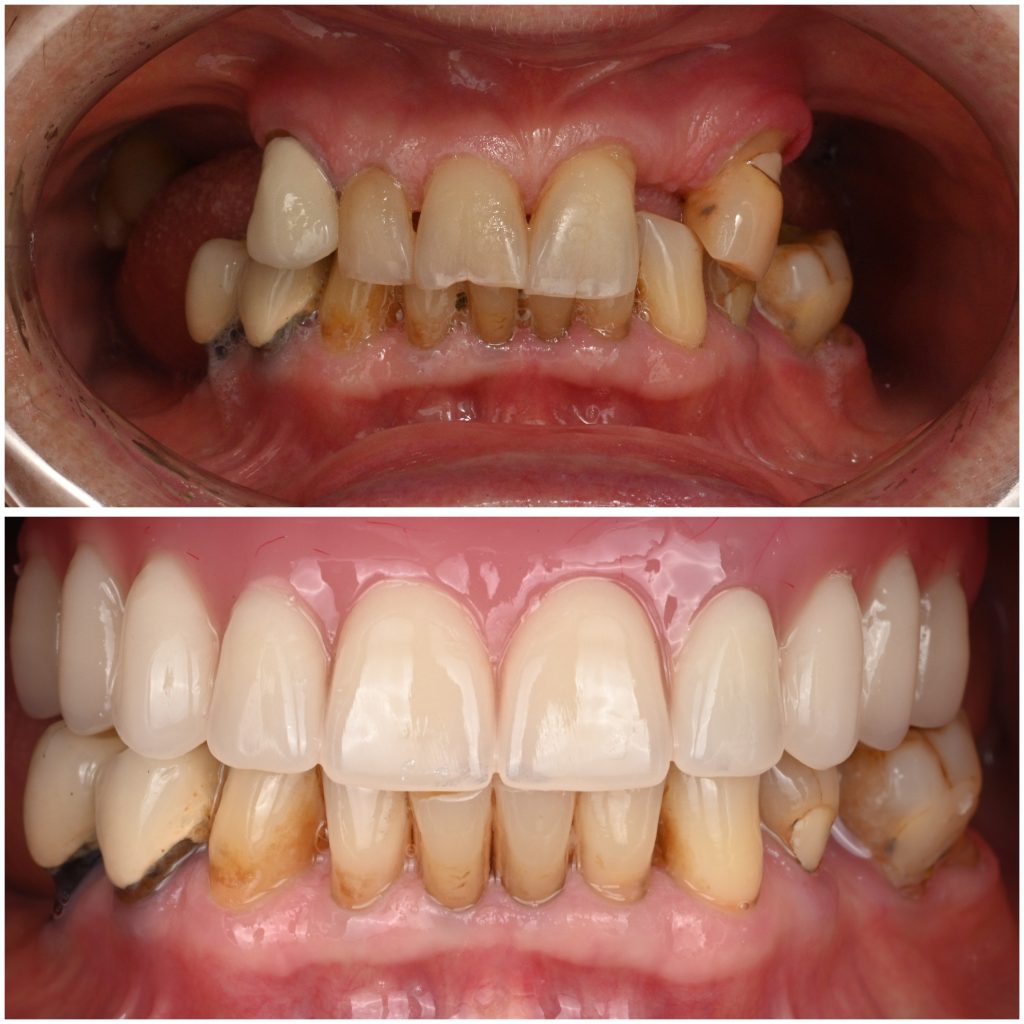

Имплантация All-on-4 в нашей клинике в Москве — это современная методика восстановления всех зубов на одной челюсти с опорой всего на четыре импланта. Технология позволяет получить несъёмные зубы даже при полном отсутствии зубов и выраженной атрофии костной ткани.

Метод позволяет быстро вернуть эстетику и жевательную функцию.

Преимущества All-on-4

- Восстановление всей челюсти на 4 имплантах..

- Возможность фиксации временного протеза в день операции (по показаниям).

- Отсутствие съёмной конструкции.